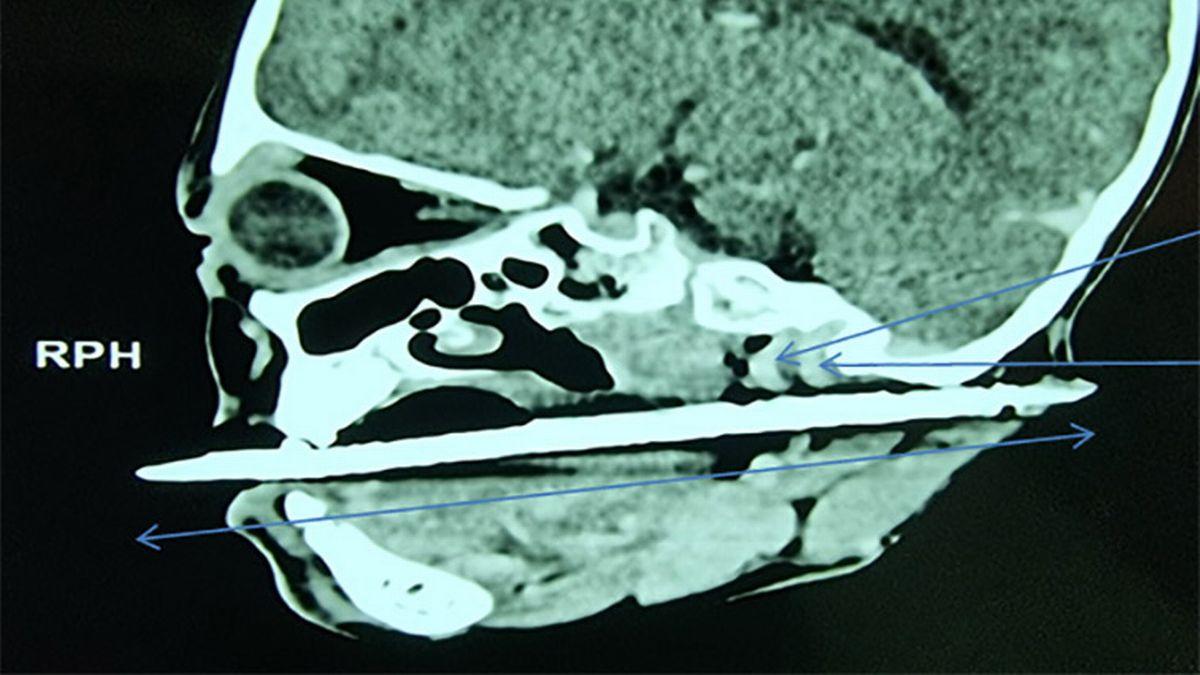

На рентгеновском снимке видно, что большая заколка проникла изо рта ребенка в район затылка.

Сканирование шеи и лица ребенка показало, что металлический предмет находится в контакте или рядом с внутренней сонной артерией и яремными венами, а также выходит прямо за ухом.